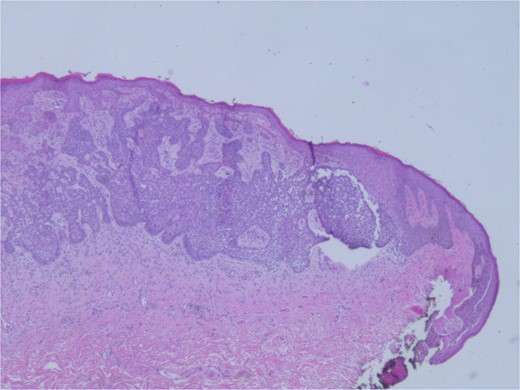

At the time of the surgery, the lesion was excised with 5 mm margins, given the acceptable margins of 4 mm for nonmelanoma skin cancer [4]. Macroscopic examination of the lesion revealed a well-defined, hyperpigmented, macular lesion with pathology positive for infiltrating BSC with negative margins confirmed on histology. Histology was notable for predominantly basal cell morphology with areas of squamous differentiation. The presence of the basal cell carcinoma component is demonstrated (Fig. 1). The BSC with abnormal squamous keratinization is also demonstrated (Figs 2–4). These studies were conducted on routine hematoxylin and eosin stains confirming the diagnosis of BSC. The patient was seen in the office, and at 2 months postoperative, there were no clinical concerns.

Microphotograph revealing basal cell carcinoma component on histology.